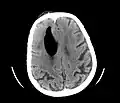

Large pneumocephaly secondary to surgical wound -

Pneumocephaly